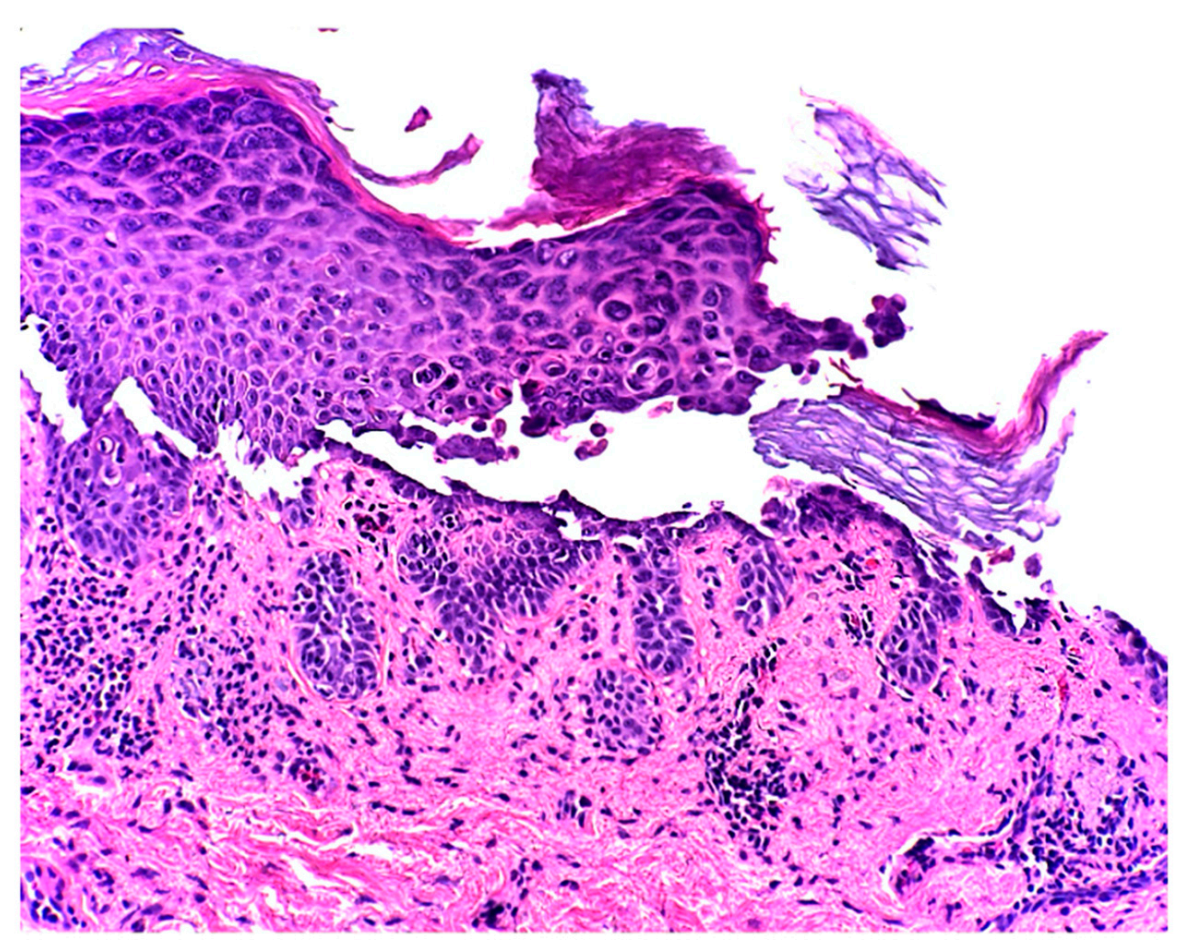

2. Case Report